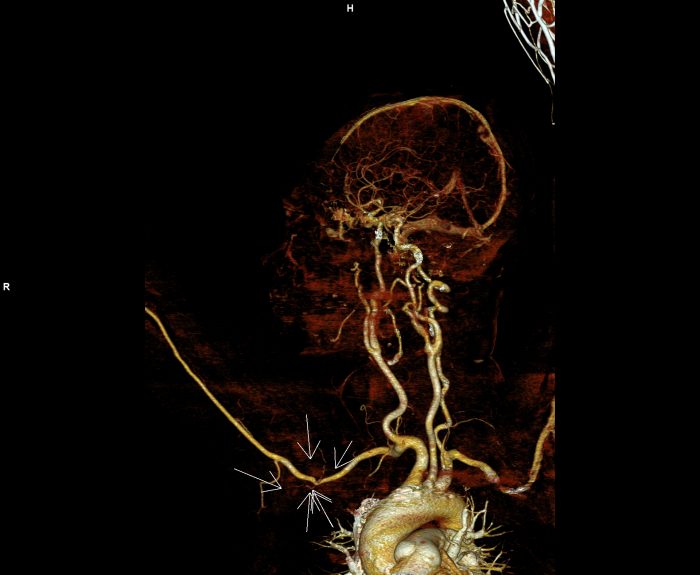

Figura 1: reconstrucție de volum din achiziție în timp arterial cu evidențierea modificării de calibru a arterei axilare

Discuţie caz nr 40: pacienta cunoscută cu neoplasm mamar este trimisă la examinare angioCT pentru suspiciune ecografică de tromboză de venă axilară dreapta. Se evidențiază o leziune expansivă densă cu priză de contrast în timp venos situată în vârful axilei drept care invadează pachetul vascular axilar determinând reducere de calibru a arterei axilare drepte și ocluzia venei axilare drepte cu dezvoltare de circulație colaterală de tip venos  la nivelul țesutului subcutanat al hemitoracelui drept și în musculatura paravertebrala posterioară.